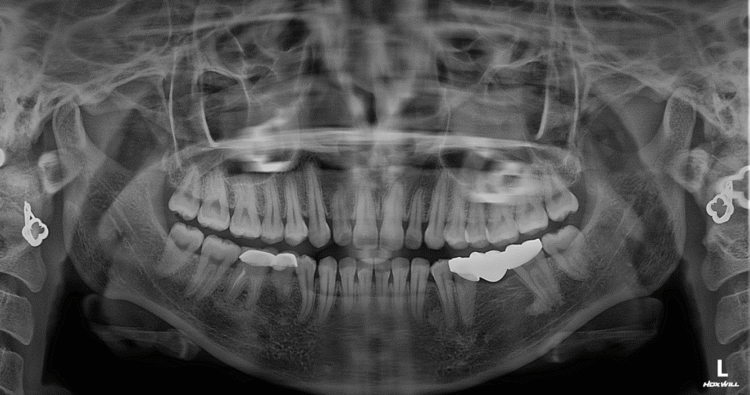

Chụp phim khi trồng răng có tác dụng gì? Vì sao cần thiết trước khi cấy Implant?

Chụp phim X-quang trước khi trồng răng giúp bác sĩ xác định chính xác thể tích xương, vị trí thần kinh, xoang hàm và ...[Xem thêm]